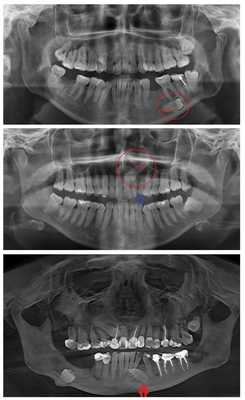

Диагностика

Диагностика полуретинированного зуба незатруднительна: при стоматологическом осмотре над десной выявляется верхушка зуба, контуры зуба определяются при пальпации, коронка обнаруживается при зондировании. Ретинированный зуб может быть достоверно обнаружен только с помощью прицельной рентгенографии или ортопантомографии; в некоторых случаях требуется проведение компьютерной томографии. Полуретинированный зуб с отложениями зубного налета или зубного камня может быть ошибочно принят за корень зуба, пораженный кариесом.

КТ челюстно-лицевой области (3D-реконструкция). Непрорезавшийся ретинированный клык верхней челюсти справа, расположенный под углом в толще альвеолярного отростка.

Найти полностью ретинированные зубы - это настоящий квест. Их может быть вообще не видно, потому что они расположились под существующими элементами зубного ряда. В таком случае вариант диагностики только один: необходимо делать полный снимок челюсти, на котором будет отлично видно всю картину. Ниже на картинке - подборка примеров. Ретинированные зубы отмечены красным или стрелками.

Примеры ретинированных зубов на рентгеновском снимке